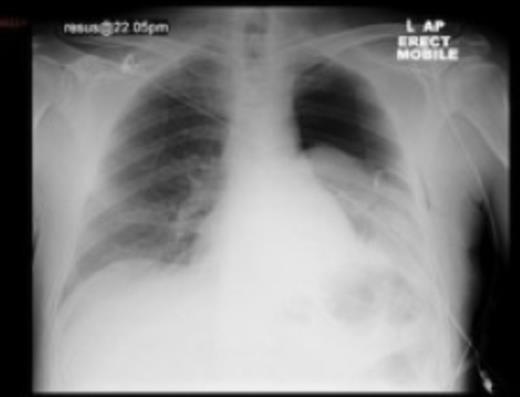

A tube thoracostomy was performed, which drained approximately 300ml of purulent fluid. The follow-up chest X-ray (Fig. 1) showed a persistent pneumothorax although the appearances had improved and the mediastinum was centrally positioned. In view of his on-going abdominal complaints, an abdominal X-ray was obtained. This showed markedly dilated large bowel within the upper abdomen, consistent with large bowel obstruction. A surgical review confirmed him to be distended, tympanic, with upper abdominal tenderness and scanty bowel sounds. A CT scan of the chest and abdomen was requested.